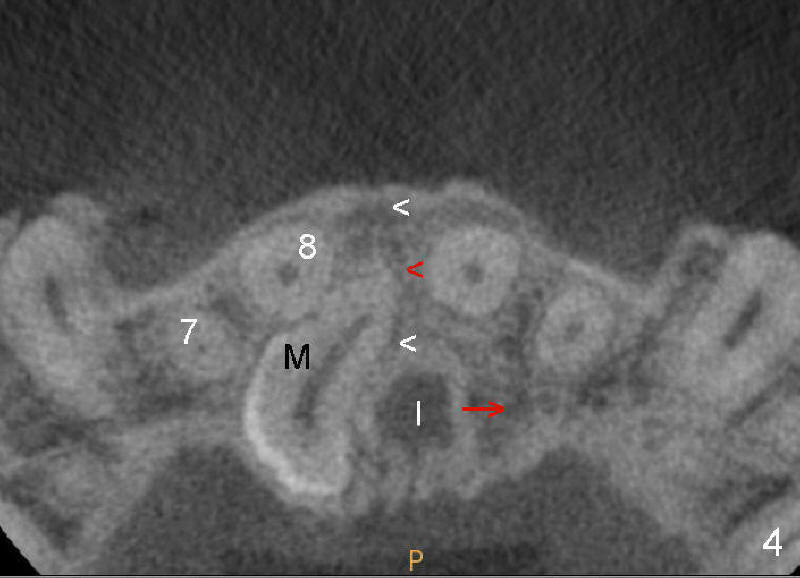

When a 39-year-old man presents for new patient exam and possible orthodontic treatment, PA shows a mesiodens associated with #8. Without careful basic exam, CBCT is ordered to determine surgical approach.

CBCT shows that the crown of the mesiodens is palatal (Fig.4: P). Second visual exam of the palate demonstrates an elevation (Fig.3: M) lateroposterior to the incisal papilla (*, a midline structure). It appears that CBCT is not so critical in deciding surgical approach for this case.